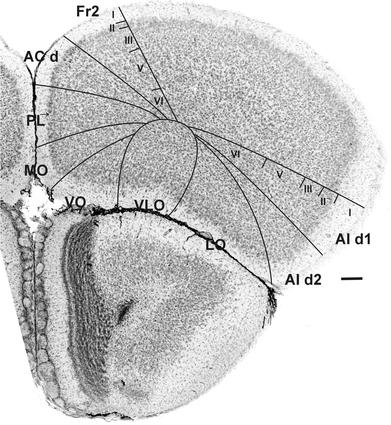

Cytoarchitectonic and chemoarchitectonic characterization of the prefrontal cortical areas in the mouse.

This study describes cytoarchitectonic criteria to define the prefrontal cortical areas in the mouse brain (C57BL/6 strain). Currently, well-illustrated mouse brain stereotaxic atlases are available, which, however, do not provide a description of the distinctive cytoarchitectonic characteristics of individual prefrontal areas. Such a description is of importance for stereological, neuronal tracing, and physiological, molecular and neuroimaging studies in which a precise parcellation of the prefrontal cortex (PFC) is required. The present study describes and illustrates: the medial prefrontal areas, i.e., the infralimbic, prelimbic, dorsal and ventral anterior cingulate and Fr2 area; areas of the lateral PFC, i.e., the dorsal agranular insular cortical areas and areas of the ventral PFC, i.e., the lateral, ventrolateral, ventral and medial orbital areas. Each cytoarchitectonically defined boundary is corroborated by one or more chemoarchitectonic stainings, i.e., acetylcholine esterase, SMI32, SMI311, dopamine, parvalbumin, calbindin and myelin staining.